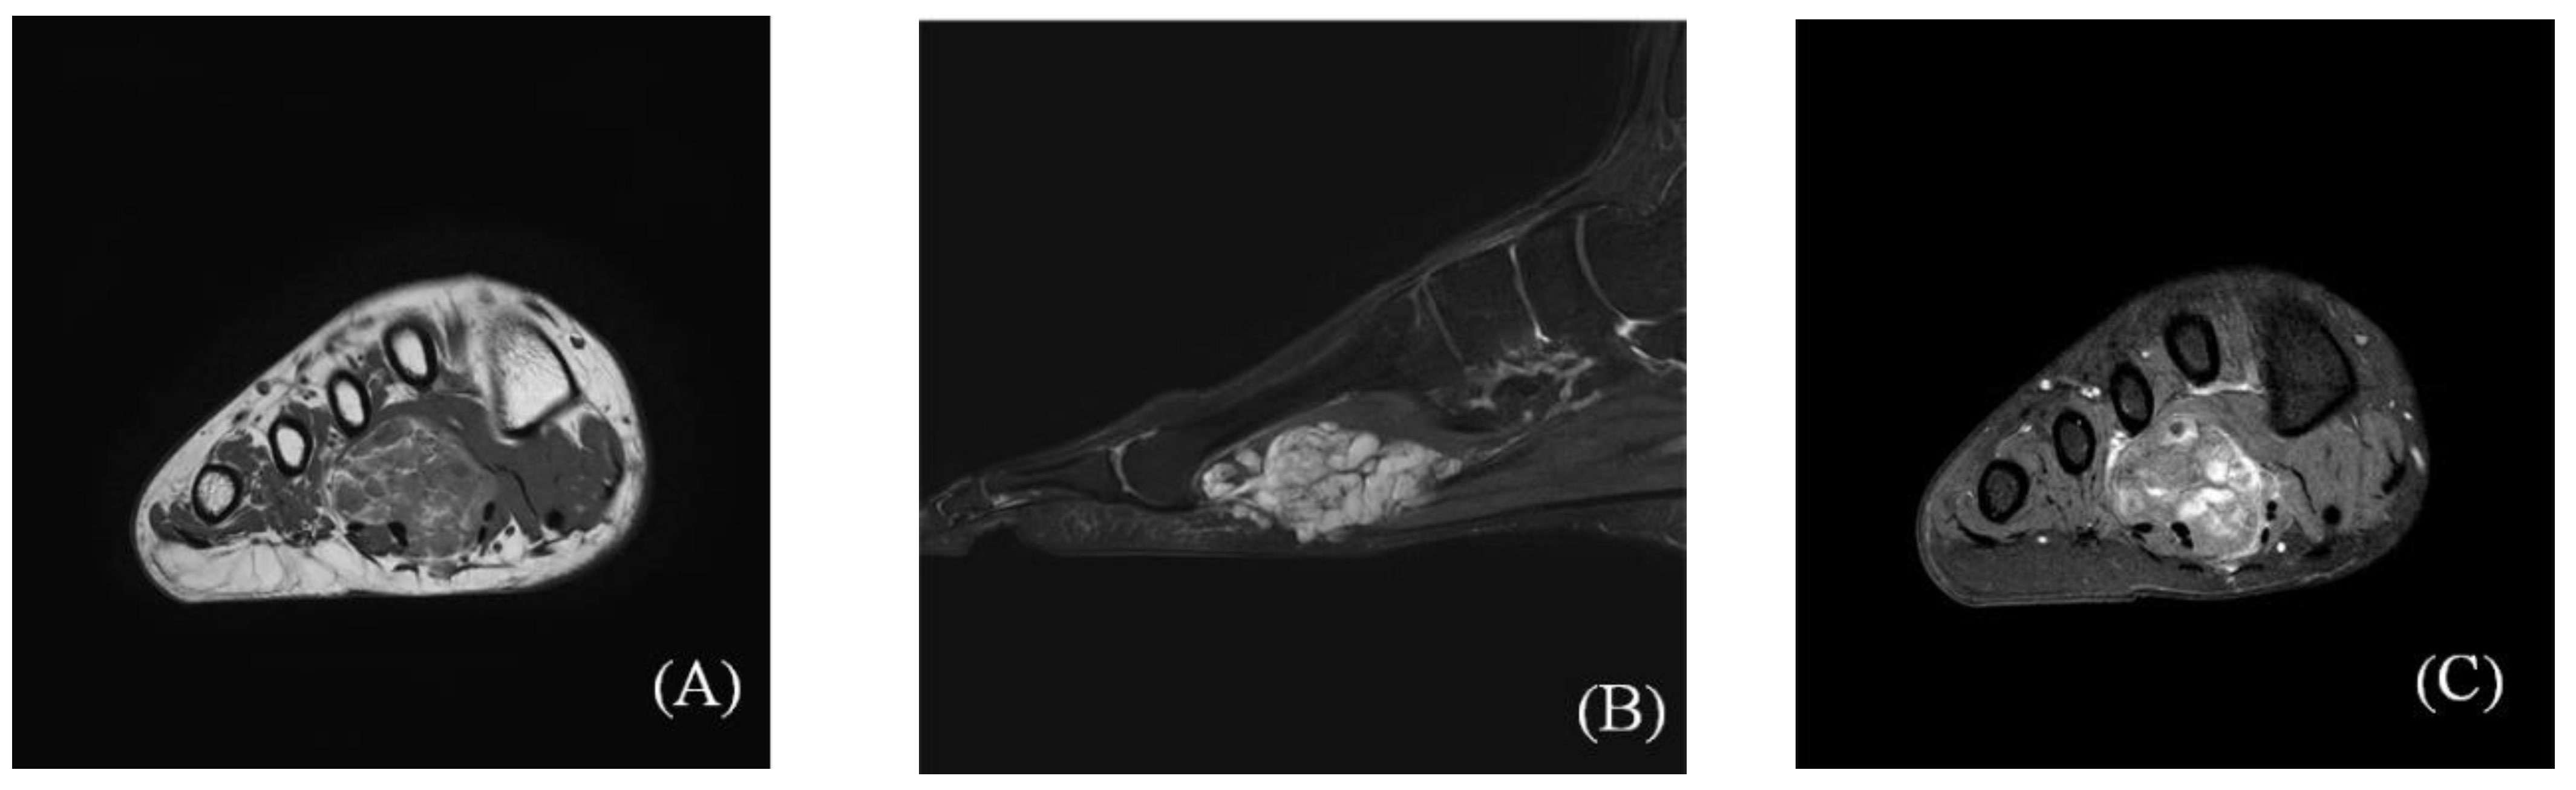

2.1. Preoperative Evaluation